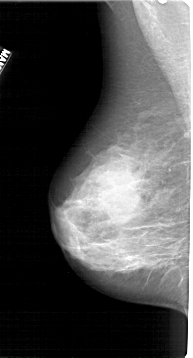

A_1270_1.RIGHT_MLO

RIGHT_MLO LINES 5491 PIXELS_PER_LINE 2791 BITS_PER_PIXEL 12 RESOLUTION 43.5 OVERLAY